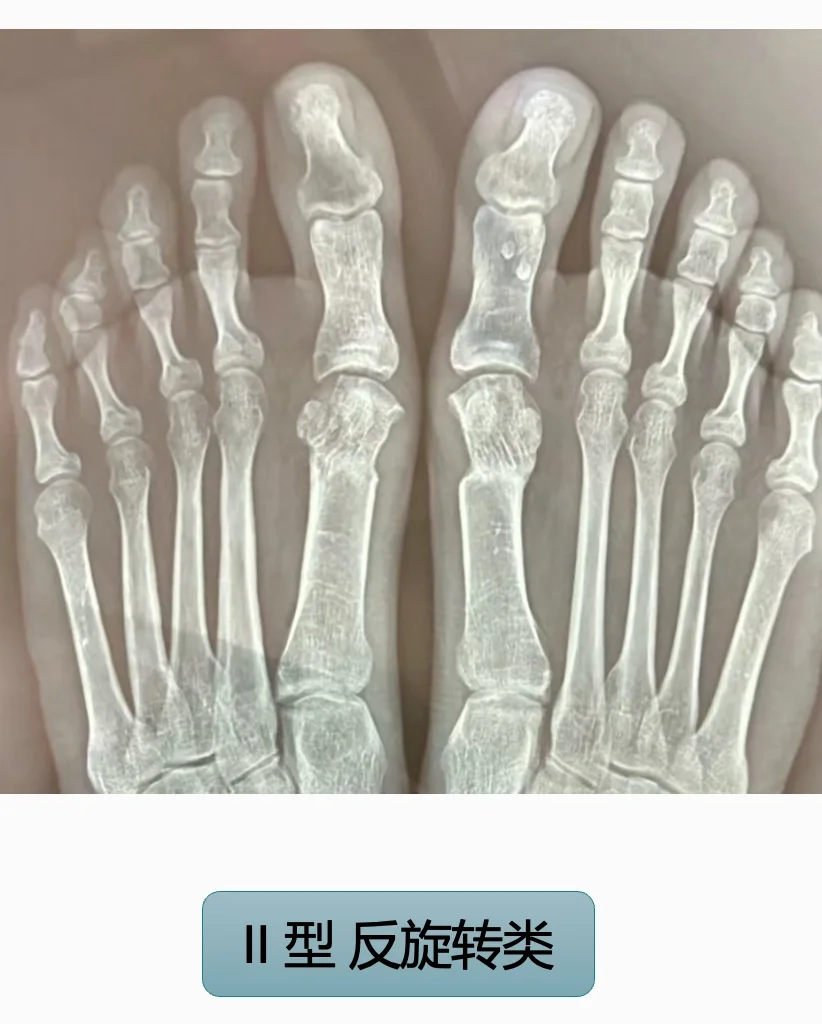

II型:断骨反旋转,关节匹配不良,不舒服但功能尚可,也有不想修的,主要看症状。

翻修方案已经确定解决,翻修相对简单可靠,需要重新断骨调整,术后效果良好。